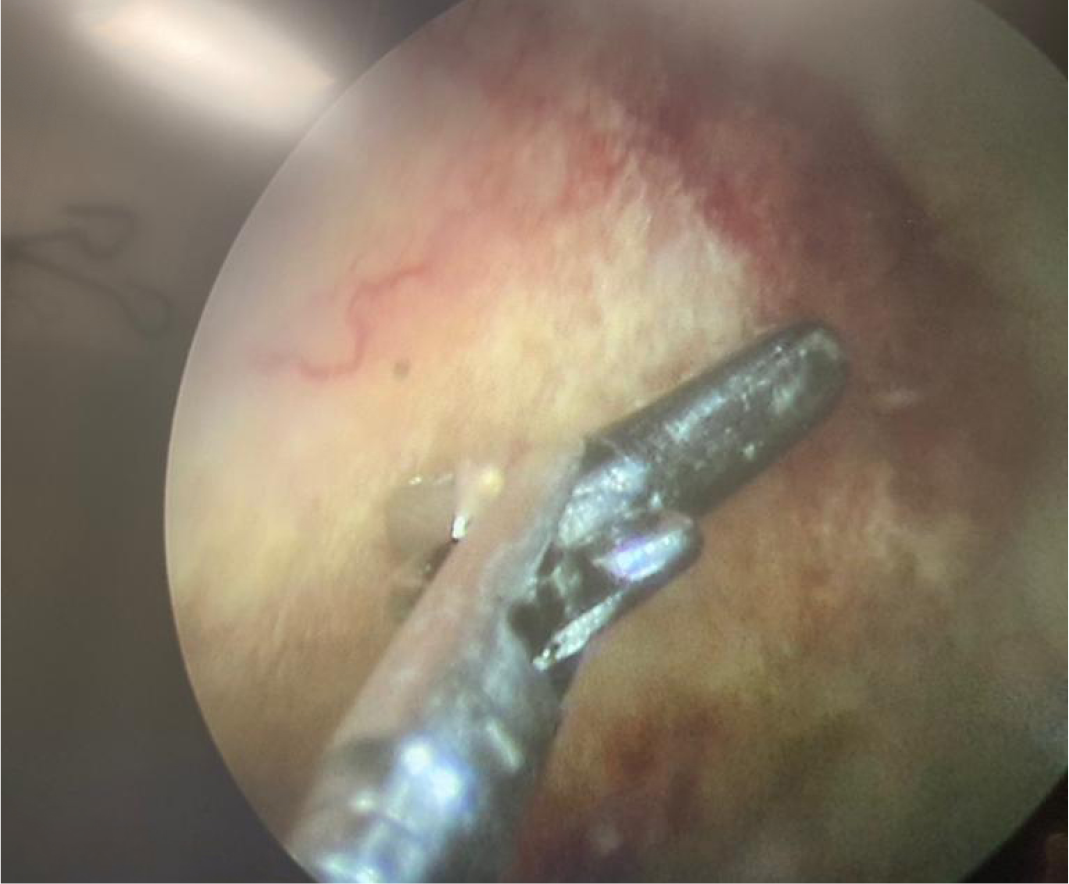

Solid oluşum olması üzerine üroloji ile konsülte edilen hastaya sistoskopi planlandı. Sistoskopide, mesane anterior superior duvarında yaklaşık 2×1 cm’lik papülonoduler lezyon görüldü (Resim 1-2). Lezyondan alınan biyopsi materyalinde lamina propriada parazitik infiltrasyon saptandı ve şiştozoma ile uyumlu olarak raporlandı (Resim 3). Eş zamanlı olarak mikrobiyoloji laboratuvarına gönderilen idrar örneğinde parazit yumurtaları tespit edildi (Resim 4). Hastaya praziquantel 2×40 mg/kg verildi. Bir ay sonra şikayetleri geçen hastanın kontrol idrar tetkikinde özellik yoktu. Sistoskopiyi kabul etmeyen hasta ülkesine döneceği için tekrar kontrole gelmedi.